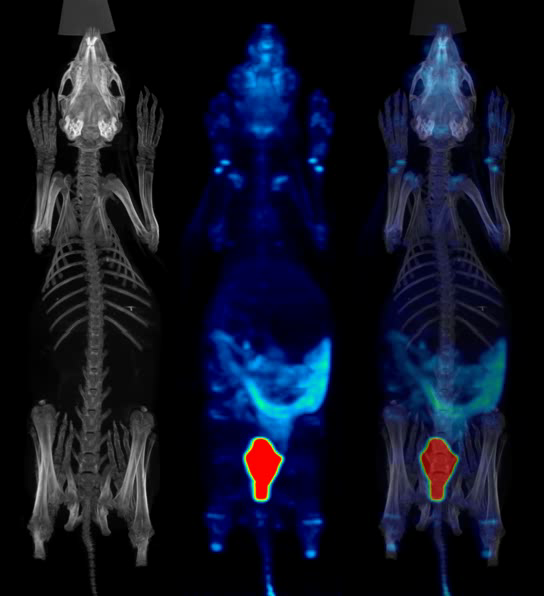

Rabbit with weight of 181g, 18F-FDG NR_iter15_sub_1 4床位拼床

330g 兔子耳缘静脉注射18F-FDG 1.03mCi 60分钟后,每床位采集15分钟,共3床位 / 195g 兔子耳缘静脉注射18F-FDG 190uci 35分钟后,单床位采集2小时